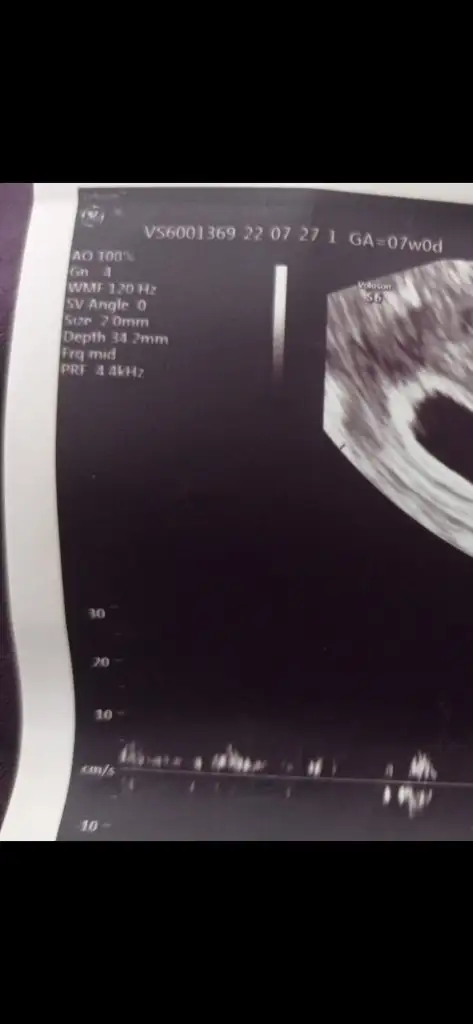

Öncelikle tebrikler kuzum. Size 2mm demiş ama o bebeğin mi büyüklüğü yoksa kesenin mi bilemedim. Tek foto mu verdiler sana bana 4lü vermişlerdi her birinde başka bi ölçüm yazıyordu. Kalp atışı da o Hz yazan değil yanında bpm yazan yani 121 bpm. BPM (Beat per Minute demek) dakika başına düşen kalp atışı. Hz frekans değerini gösteriyor sana ultrasonla gönderilen ya da senden geri seken frekans.

Sagol canm bende anlamadım merak ettim sordum 2 foto ama diğerinde birşey yazmıyor bakim tekrar bi ama kalp atışı için yanlış yere bakmışım ben teşekkür ederim 🥰